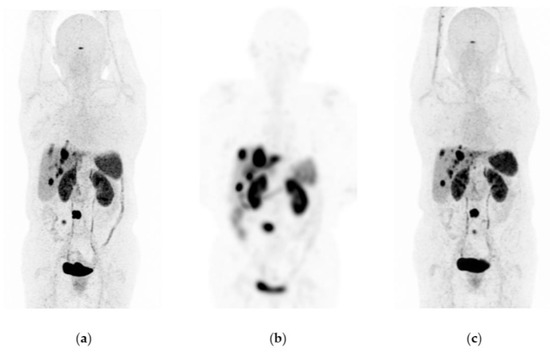

Figure 2. Patient with progressive and metastatic castration-resistant prostate cancer (mCRPC): (a) 68Ga-iPSMA PET/CT imaging before 177Lu-iPSMA therapy; initial levels of hemoglobin (15.5 g/dL), leucocytes (5700/µL), creatinine (0.82 mg/dL), platelets (238,000/µL), and serum PSA (129 ng/mL). (b) 177Lu-iPSMA SPECT imaging (first dose). (c) 68Ga-iPSMA PET/CT imaging eight months after the first 177Lu-iPSMA dose was administered; levels of hemoglobin (13.4 g/dL), leukocytes (3900/µL), creatinine (0.79 mg/dL), platelets (277,000/µL), and serum PSA (1.5 ng/mL). The patient responded completely to 177Lu-iPSMA therapy (four doses every six weeks; 7.4 GBq/dose).

177Lu-iPSMA showed an overall response rate of 36.6% (Table 2). Figure 2 and Figure 3 show typical clinical cases of complete response (disappearance of all lesions or adenopathies less than 10 mm short axis) and partial response (decrease of at least 30% in the sum of the largest diameters of lesions compared with the baseline study) after 177Lu-iPSMA therapy. In addition, the reduction of large tumors and multiple metastatic lesions are proof of the high specificity and molecular recognition of 177Lu iPSMA by PSMA at the tumor cell level (Appendix A) (Figure A1, Figure A2 and Figure A3).

Patients with mPC who received three to five doses of 177Lu-iPSMA showed an overall survival of 660 days (21.7 months) (Table 2; Figure 1a) with decreased radiotracer tumor uptake (SUV) and PSA level in 80% (n = 33) and 73% (n = 30) of the subjects, respectively (Table 2). Specifically, 52% of cases had a PSA decline of >50% after completing treatment.

The hazard ratio was 0.5650 (95% CI: 0.3391–0.9412), indicating a 43.5% reduction in the risk of death in favor of the 177Lu-iPSMA group (Table 2). In addition, 50% of patients were free of progression at 323 d (10.6 months) after treatment (Figure 1b).